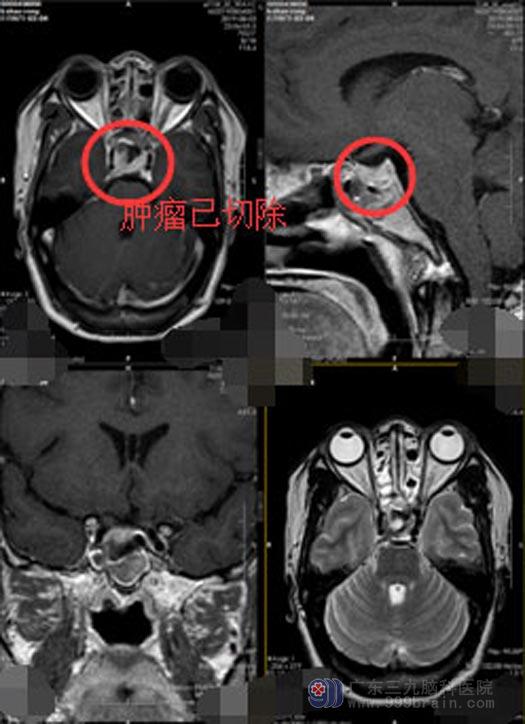

完善相关检查与术前准备后,由鲁明主任主刀行“神经内镜下经鼻蝶鞍区占位切除术”,手术很顺利,脑瘤被完整的切除。几天后,李女士便顺利出院。回访时,李女士在电话里高兴地告诉医生:左邻右舍都看不出来我是做过手术的人。

▲手术后

神经内镜技术具有创伤小、视角灵活等优点,其灵活的“多视角观察”及“鱼眼效应”能让术者更近距离的以宽阔视野观察鞍内结构,最大程度的保留垂体功能、避免损伤。神经内镜进入鞍内观察瘤腔深部和侧壁残留的肿瘤组织,甚至可以观察到鞍旁和鞍上的部分肿瘤,增加了全切率。曾做为垂体手术主导术式的显微镜下的经蝶手术已逐渐向内镜下鼻内经蝶手术过渡,神经内镜下经鼻蝶垂体瘤切除术是目前首选的诊疗方式。